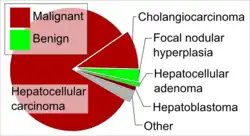

Liver tumors (also known as hepatic tumors) are abnormal growth of liver cells on or in the liver. Several distinct types of tumors can develop in the liver because the liver is made up of various cell types.[1] Liver tumors can be classified as benign (non-cancerous) or malignant (cancerous) growths. They may be discovered on medical imaging (even for a different reason than the cancer itself), and the diagnosis is often confirmed with liver biopsy.[2] Signs and symptoms of liver masses vary from being asymptomatic to patients presenting with an abdominal mass, hepatomegaly, abdominal pain, jaundice, or some other liver dysfunction. Treatment varies and is highly specific to the type of liver tumor.[3]

Liver tumors can be broadly classified as benign or malignant:

Cancerous

- Most cases are metastases from other tumors, frequently of the GI tract (like colon cancer, carcinoid tumors mainly of the appendix, etc.), but also from breast cancer, ovarian cancer, lung cancer, renal cancer, prostate cancer, etc.

- The most frequent, malignant, primary liver cancer is hepatocellular carcinoma.[13]

- Other forms of primary forms of liver cancer include cholangiocarcinoma, mixed tumors, sarcoma, and hepatoblastoma.